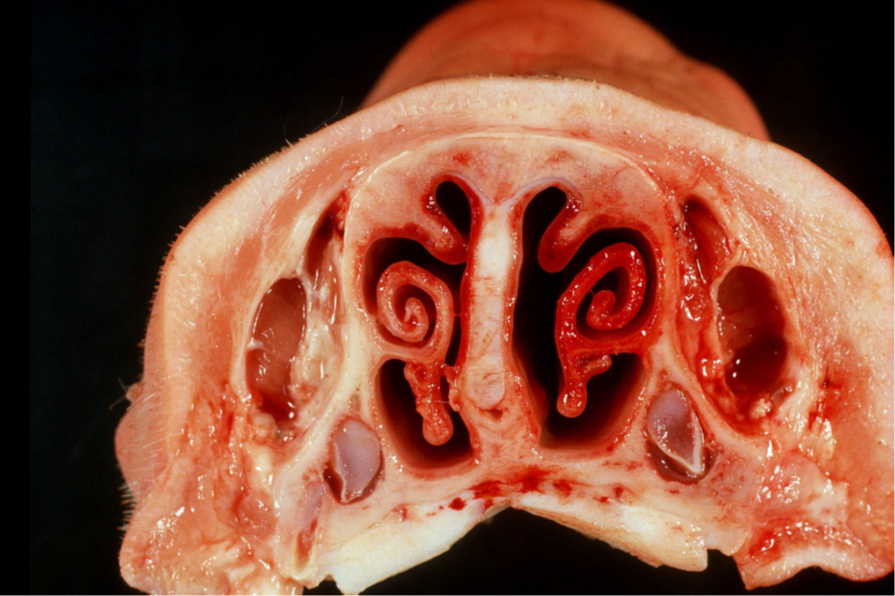

Schwein, Nase, Rhinitis atrophicans

Beschreibung:

•die ventrale Spirallamelle ist fast vollständig geschwunden

• Deviation des Septums

Hintergrundwissen/ Infektionsweg/ Pathogenese

Die Rhinitis atrophicans ist meldepflichtig

Ätiologie: Pasteurella multocida Typ D und/oder Bordetella bronchiseptica

Jeweils Stämme, die ein sog. dermatonekrotisches Toxin bilden (ein hitzelabiles zytoplasmatisches Toxin; das gereinigte Toxin löst, selbst

nach parenteraler Gabe in die Oberschenkelmuskulatur, eine R. a. beim Schwein aus

Pathogenese:

Es kommt zur Besiedlung des respiratorischen Epithels der Nase; das Toxin beeinflußt das Knochenwachstum, d.h. die Osteoblasten;

besonders empfindlich sind Knochen mit einer hohen Wachstumsrate; dazu zählen vor allem die Knochen der Nasenmuscheln; die Folge ist

eine Wachstumstörung und weniger der Schwund von voll ausgebildetem Knochen (d.h. die Krankheit tritt bei nur Tieren in der

Wachstumsphase auf). Der Abbau von Knochen erfolgt nicht unmittelbar durch das Entzündungsgewebe, das in der Propria der

Nasenschleimhaut ebenfalls auftritt; die Verbiegung des Nasenseptums (Deviation) und des Angesichtsschädels kommt durch eine

unterschiedlich starke Wachstumshemmung zustande

Folgen:

Aufgrund von bakt. Sekundärinfektionen katarrh.-eitriger Nasenausfluß bis zu Nasenbluten; im fortgeschrittenen Stadium Deformation des

Gesichtsschädels mit:

a. Verbiegung des Nasenseptums (in Längsrichtung)

b. seitlicher Deviation

c. Verkürzung des Angesichtsschädels (Faltenbildung am Nasenrücken)